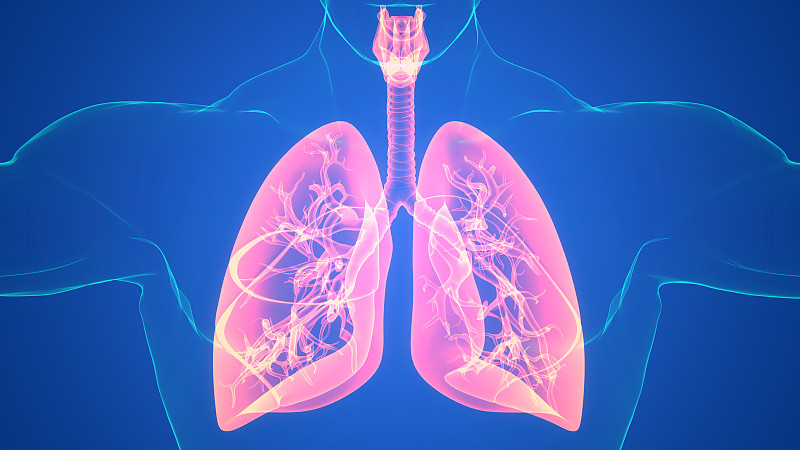

人体呼吸系统肺解剖学详情

JPG